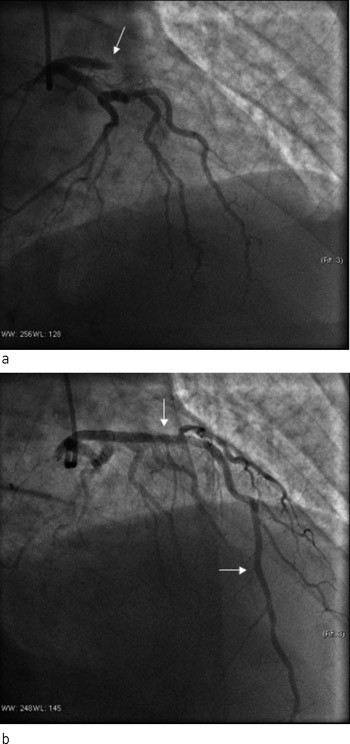

Pasienten ble flyttet tilbake til lokalsykehuset i påvente av koronaroperasjonen. Dag 14 fikk pasienten nye smerter og EKG-forandringer forenlig med okkludert venstre fremre koronararterie. Han ble på ny overflyttet til Oslo universitetssykehus, Ullevål, der det for tredje gang ble påvist stenttrombose. Okklusjonen ble åpnet med ballongdilatasjon uten ny stentimplantasjon. Han fikk ufraksjonert heparin og abciximab under prosedyren. En time etter avsluttet prosedyre tilkom spontanblødninger fra nese, gastrointestinalkanalen, urinveier og alle innstikksteder på kroppen. Blodprøvene viste nå trombocyttverdi 2 x 10⁹/l, som var en drastisk nedgang fra verdien målt tidligere samme dag på lokalsykehuset (187 x 10⁹/l) (fig 2). Troponin T-verdien var 3,2 µg/l og hemoglobinnivået 13,1 g/dl, synkende til 9,8 g/dl. Abciximab ble øyeblikkelig seponert. Han fikk deretter totalt fire enheter platekonsentrat, og man «nullet ut» klopidogrel. Ved denne behandlingen steg trombocyttene til ca. 60 x 10⁹/l og deretter spontant til 136 x 10⁹/l. Etter stabilisering av situasjonen valgte man å gi heparin som kontinuerlig infusjon. Dette var vellykket. Trombocyttallet fortsatte å stige. Pasienten gjennomgikk koronaroperasjon med bruk av hjerte-lunge-maskin og heparin 20 dager etter første hjerteinfarkt. Han ble utskrevet til sitt lokalsykehus for videre oppfølging av koronarsykdom og mistenkt kreftsykdom. Tumoren i urinblæren viste seg å være et lavgradig, malignt karsinom uten muskelinvasivitet, og radikalbehandling er under planlegging.